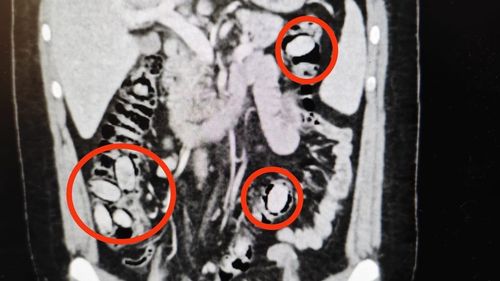

Kent girişindeki kontrolde şüphe üzerine durdurulan S.A. (25), midesinde 44 kapsül metamfetamin taşıdığı tespit edilip ameliyatla çıkarıldı ve tutuklandı.

Eskişehir'de midesinde 44 kapsül metamfetamin taşıyan yabancı uyruklu şahıs tutuklandıPolisin dikkatiyle başlayan operasyon cerrahi müdahaleyle sonuçlandıYurtdışından Eskişehir'e gelen S.A. (25) isimli yabancı uyruklu şahıs, kent girişindeki çevirme noktasında görevli polislerin dikkatinden şüphe çekti. Kontrol sürecinde durumunda anormallikler fark edilmesi üzerine…